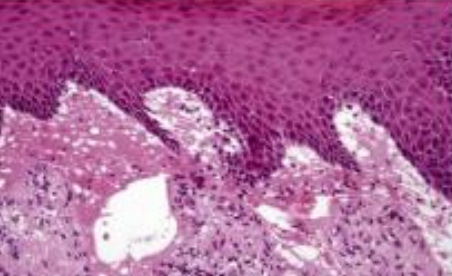

Hereditary Benign Intraepithelial Dyskeratosis

(HBID, Witkop’s disease)

體顯性

GENE: 4q35端粒, NLRP1, M77T

口腔與結膜黏膜,孩童

• 類似Cannon disease

• 眼睛: 不透明凝膠狀斑塊

• 舌背: 通常沒有影響

• hyperparakeratosis, acanthosis

• upper spinous layer 局部角化

• ell-within-a- cell